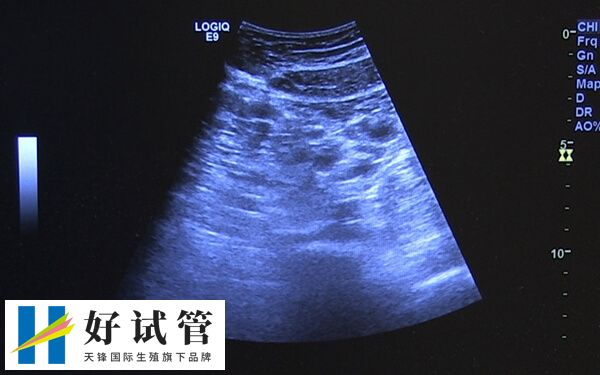

试管临床上,长方案促排卵泡治疗周期应用的比较多,不过因个体之间存在较大的差异,所以部分患者在使用长方案促排卵之后,可能会出现卵泡大小不一样的情况,而这也可能是以下几点导致的。

长方案促排卵泡大小不匀称可能由多种因素导致,比如说患者如果存在卵巢功能减退,那么由于雌激素和孕激素的异常,通常会导致FSH提前升高,这就会使卵泡发育不均,进而出现有些卵泡过于成熟,而有效卵泡则为小卵泡等情况。